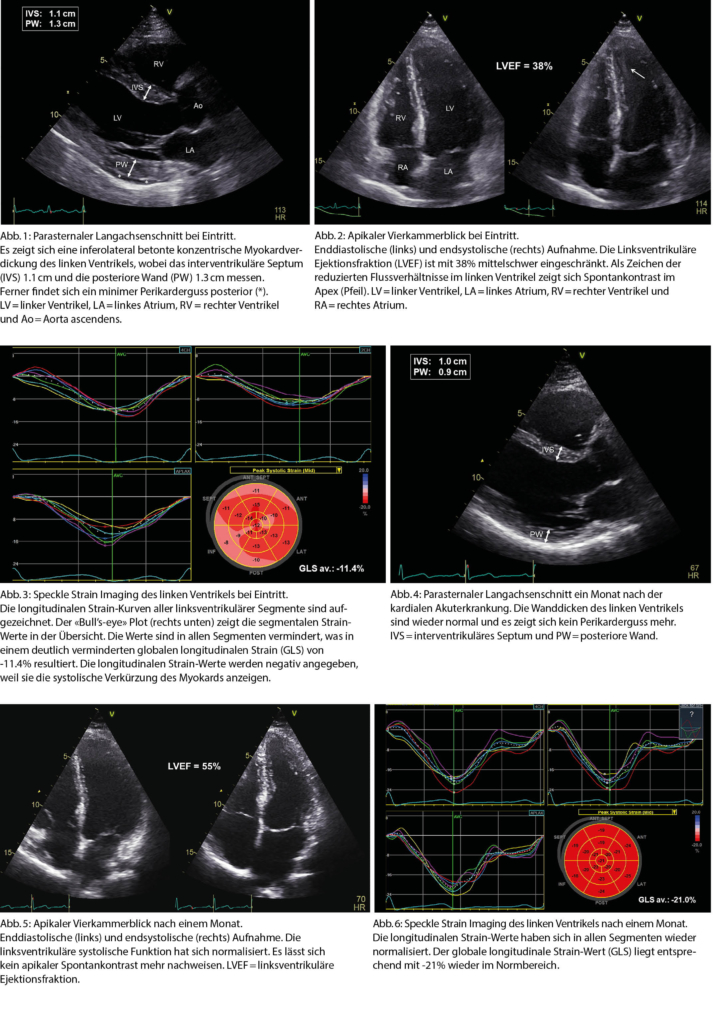

Eine 33-jährige Patientin musste wegen einer schweren paranoiden Schizophrenie in einer psychiatrischen Klinik hospitalisiert werden. Es erfolgte eine medikamentöse Einstellung mit Clozapin und Amisulprid. Im Laufe der Hospitalisation klagte die Patientin über zunehmende Müdigkeit, Kopfschmerzen, Gliederschmerzen und trockenen Reizhusten. In der Folge kam es auch zu zunehmender Dyspnoe, so dass die Patientin notfallmässig ins Akutspital verlegt werden musste. Bei Eintritt war die Patientin subfebril und tachykard mit einer Herzfrequenz von 120 pro Minute. Der Blutdruck lag bei 100/50mmHg. In der klinischen Untersuchung fanden sich keine eindeutigen Stauungszeichen. Radiologisch zeigte sich eine knapp kompensierte Lungenzirkulation. Das EKG zeigte keine spezifischen Veränderungen. Im Labor fielen eine deutliche Leukozytose, ein CRP von 287 mg/l (Norm < 10) und ein hochsensitives (hs) Troponin T von 245 pg/l (Norm < 14) auf. Als zusätzliche Untersuchung wurde eine transthorakale Echokardio-graphie durchgeführt. Hierbei zeigte sich eine konzentrische linksventrikuläre (LV) Myokardverdickung, welche inferolateral betont war. Ferner fand sich ein minimer Perikarderguss (Abb. 1). Die LV Ejektionsfraktion (EF) war mit 38% mittelschwer eingeschränkt und es zeigte sich Spontankontrast im LV Apex (Abb. 2). Der globale longitudinale Strain (GLS) war mit -11.4% deutlich eingeschränkt (Abb. 3), was auf eine erhebliche Einschränkung der myokardialen Longitudinalfunktion hinwies. Aufgrund der erhobenen Befunde ergab sich das Bild einer akuten Myokarditis. An welche Ursache hierfür muss bei dieser Patientin im Besonderen gedacht werden?

Differentialdiagnostisch war einerseits eine infektiöse Genese der akuten Myokarditis denkbar. Daneben musste jedoch auch an eine Nebenwirkung von Clozapin, welches kurze Zeit vor der akuten kardialen Erkrankung initialisiert wurde, gedacht werden. Bei möglicher Clozapin-induzierter Myokarditis wurde dieses Medikament umgehend gestoppt und eine medikamentöse Herzinsuffizienztherapie eingeleitet. Fünf Tage nach Sistierung von Clozapin zeigte sich ein Rückgang des CRP auf 123 mg/l und des hs Troponins T auf 39 pg/l. Dies ging sowohl mit einer Verbesserung der LVEF auf 45%, als auch mit einer klinischen Verbesserung einher. Einen Monat später zeigte die Kontrollechokardiographie bei kardial nunmehr beschwerdefreier Patientin eine Normalisierung der Dimensionen des LV Myokards (Abb. 4), welches retrospektiv anfangs durch den entzündlichen Prozess mit konsekutivem intramyokardialem Ödem verdickt war. Ferner fanden sich eine Normalisierung der LVEF auf 55% (Abb. 5) und des GLS auf -21% (Abb. 6).